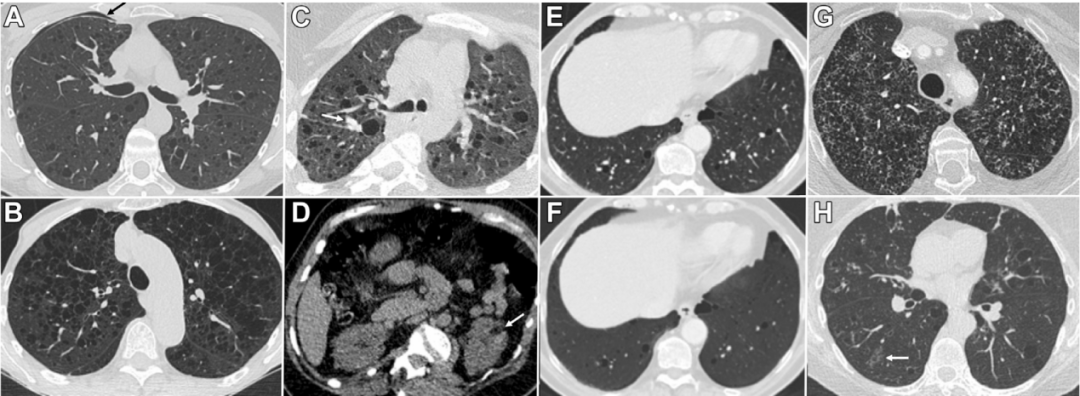

图3 A-H,CT扫描中识别的弥漫性囊性肺疾病的特征

(A)肺窗下的轴位胸部CT扫描显示一位成年女性LAM患者存在多个、散在的、薄壁肺囊,以及一个小的右侧自发性气胸(箭头所示)。

(B)一位患有严重LAM的老年女性患者,双肺广泛分布的囊性病变几乎完全替代了正常的肺实质。

(C)一位患有结节性硬化症相关LAM的成年女性患者的胸部CT扫描显示广泛的双肺囊性病变,右侧斜裂处因既往滑石粉胸膜固定术而出现高密度增厚。

(D)同一患者的腹部非增强CT扫描显示左肾前极区域约2厘米大小的脂肪密度病变(箭头所示),符合血管平滑肌脂肪瘤。

(E)一位患有Birt-Hogg-Dubé综合征的成年男性患者的胸部CT图像,显示双肺底散在分布的囊肿,呈纵隔旁及静脉周围分布模式。

(F)同一患者的最小强度投影(MinIP)CT图像。MinIP重建可以通过强调低密度体素来增加囊性病变的可见性。

(G)一位患有肺朗格汉斯细胞组织细胞增生症的成年女性,CT表现为上叶广泛不规则厚壁肺囊肿伴小叶中心性微结节。

(H)干燥综合征相关淋巴细胞性间质性肺炎成年女性患者的胸部CT,可见肺囊肿、斑片状磨玻璃影(箭头所示)及不均匀支气管壁增厚。